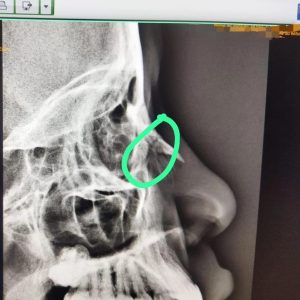

A Polícia Civil foi acionada para atender uma denúncia de violência doméstica, em que uma adolescente estaria com uma fratura no nariz, após o convivente ter arremessado um saco de carne na direção do seu rosto.